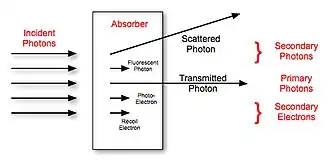

The effect of the two major interaction processes is illustrated in Figure 3.4. Photoelectric absorption of the incident photons gives rise to the generation of a photoelectrons and fluorescent X-rays, while Compton scattering generates scattered photons and recoil electrons. The transmitted photons proceed through the patient and strike the image receptor to form an image. Scattered photons can also reach the receptor - and can also be scattered in any direction around the absorber. Furthermore, some scattered photons in addition to the photoelectrons, recoil electrons and fluorescent photons loose their energy in the absorber. It is this energy loss that constitutes what is referred to as the Absorbed Dose, which we will consider in a later section of this chapter.